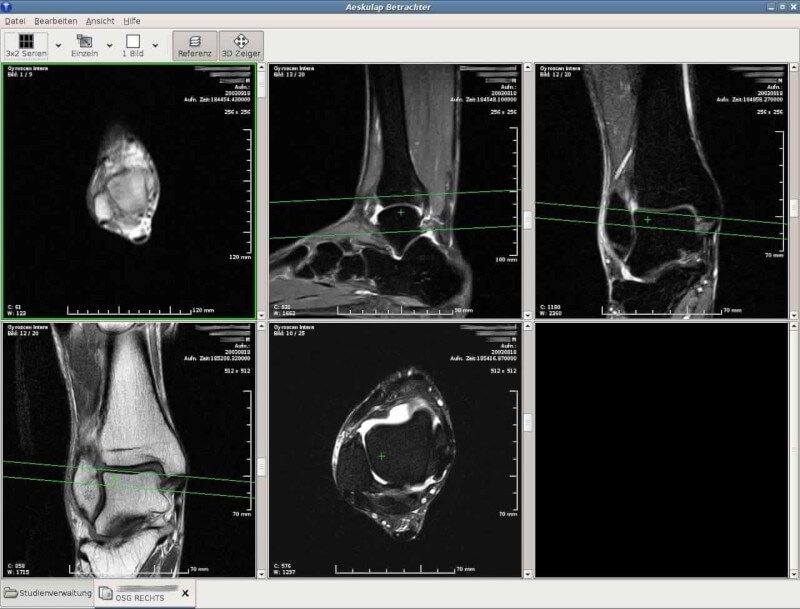

6. Aeskulap

Aeskulap is a medical image viewer that was created to be an open source alternative to commercial DICOM viewers and is based on glademm, gtkmm, and gconfmm.

It can load a series of DICOM images for review and can also fetch them from archive nodes (aka PACS) over the network.